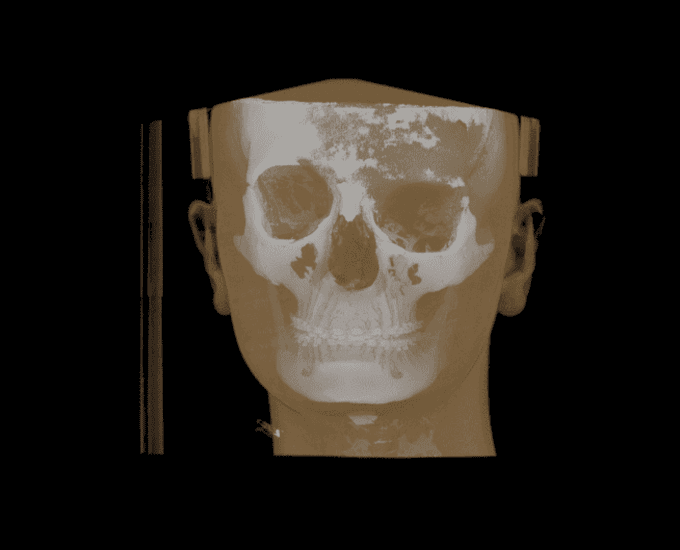

View from anywhere

Volume example 1 Volume example 2 Volume example 3 Volume example 4 Volume example 5 Volume example 6